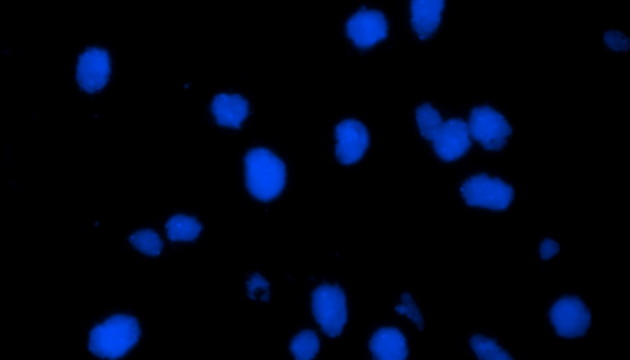

熒光原位雜交(Fluorescence In Situ Hybridization,F(xiàn)ISH)是臨床病理檢測(cè)中廣泛運(yùn)用的一種分子細(xì)胞遺傳學(xué)診斷技術(shù),其原理是用熒光染料直接或間接標(biāo)記的DNA核酸探針與待測(cè)樣本中的DNA核酸序列按照堿基互補(bǔ)配對(duì)的原則進(jìn)行雜交,然后通過熒光顯微鏡觀察熒光信號(hào)位置、數(shù)量等來判斷待測(cè)序列的缺失、擴(kuò)增及易位等情況。其高分辨率、直接反映異常細(xì)胞比例、快速簡(jiǎn)便的特點(diǎn),使其成為臨床檢測(cè)、預(yù)后評(píng)估及用藥指導(dǎo)的重要工具。

FISH技術(shù)廣泛應(yīng)用于染色體變異、基因組研究及臨床診斷。在乳腺癌、宮頸癌、膀胱癌等腫瘤中,能精準(zhǔn)檢測(cè)基因異常,指導(dǎo)靶向治療。產(chǎn)前檢測(cè)可篩查染色體異常胎兒。血液腫瘤檢測(cè)則助力預(yù)后預(yù)測(cè)與個(gè)性化治療。該技術(shù)檢測(cè)遺傳物質(zhì),標(biāo)本多樣,包括外周血、羊水、骨髓等。

FISH技術(shù)面臨熒光弱、背景噪聲、多通道疊加等難點(diǎn)。為了保障熒光信號(hào)強(qiáng)度,一般需要用到研究級(jí)熒光顯微鏡,半復(fù)消色差或以上的物鏡,以及高功率的LED熒光光源或汞燈光源;為了去除背景噪聲,一般需要搭配高截止深度的濾光片和高靈敏度相機(jī);多通道疊加時(shí)要提取紅綠信號(hào)點(diǎn),然后放到藍(lán)色DAPI信號(hào)上,處理需要相當(dāng)?shù)募记伞?